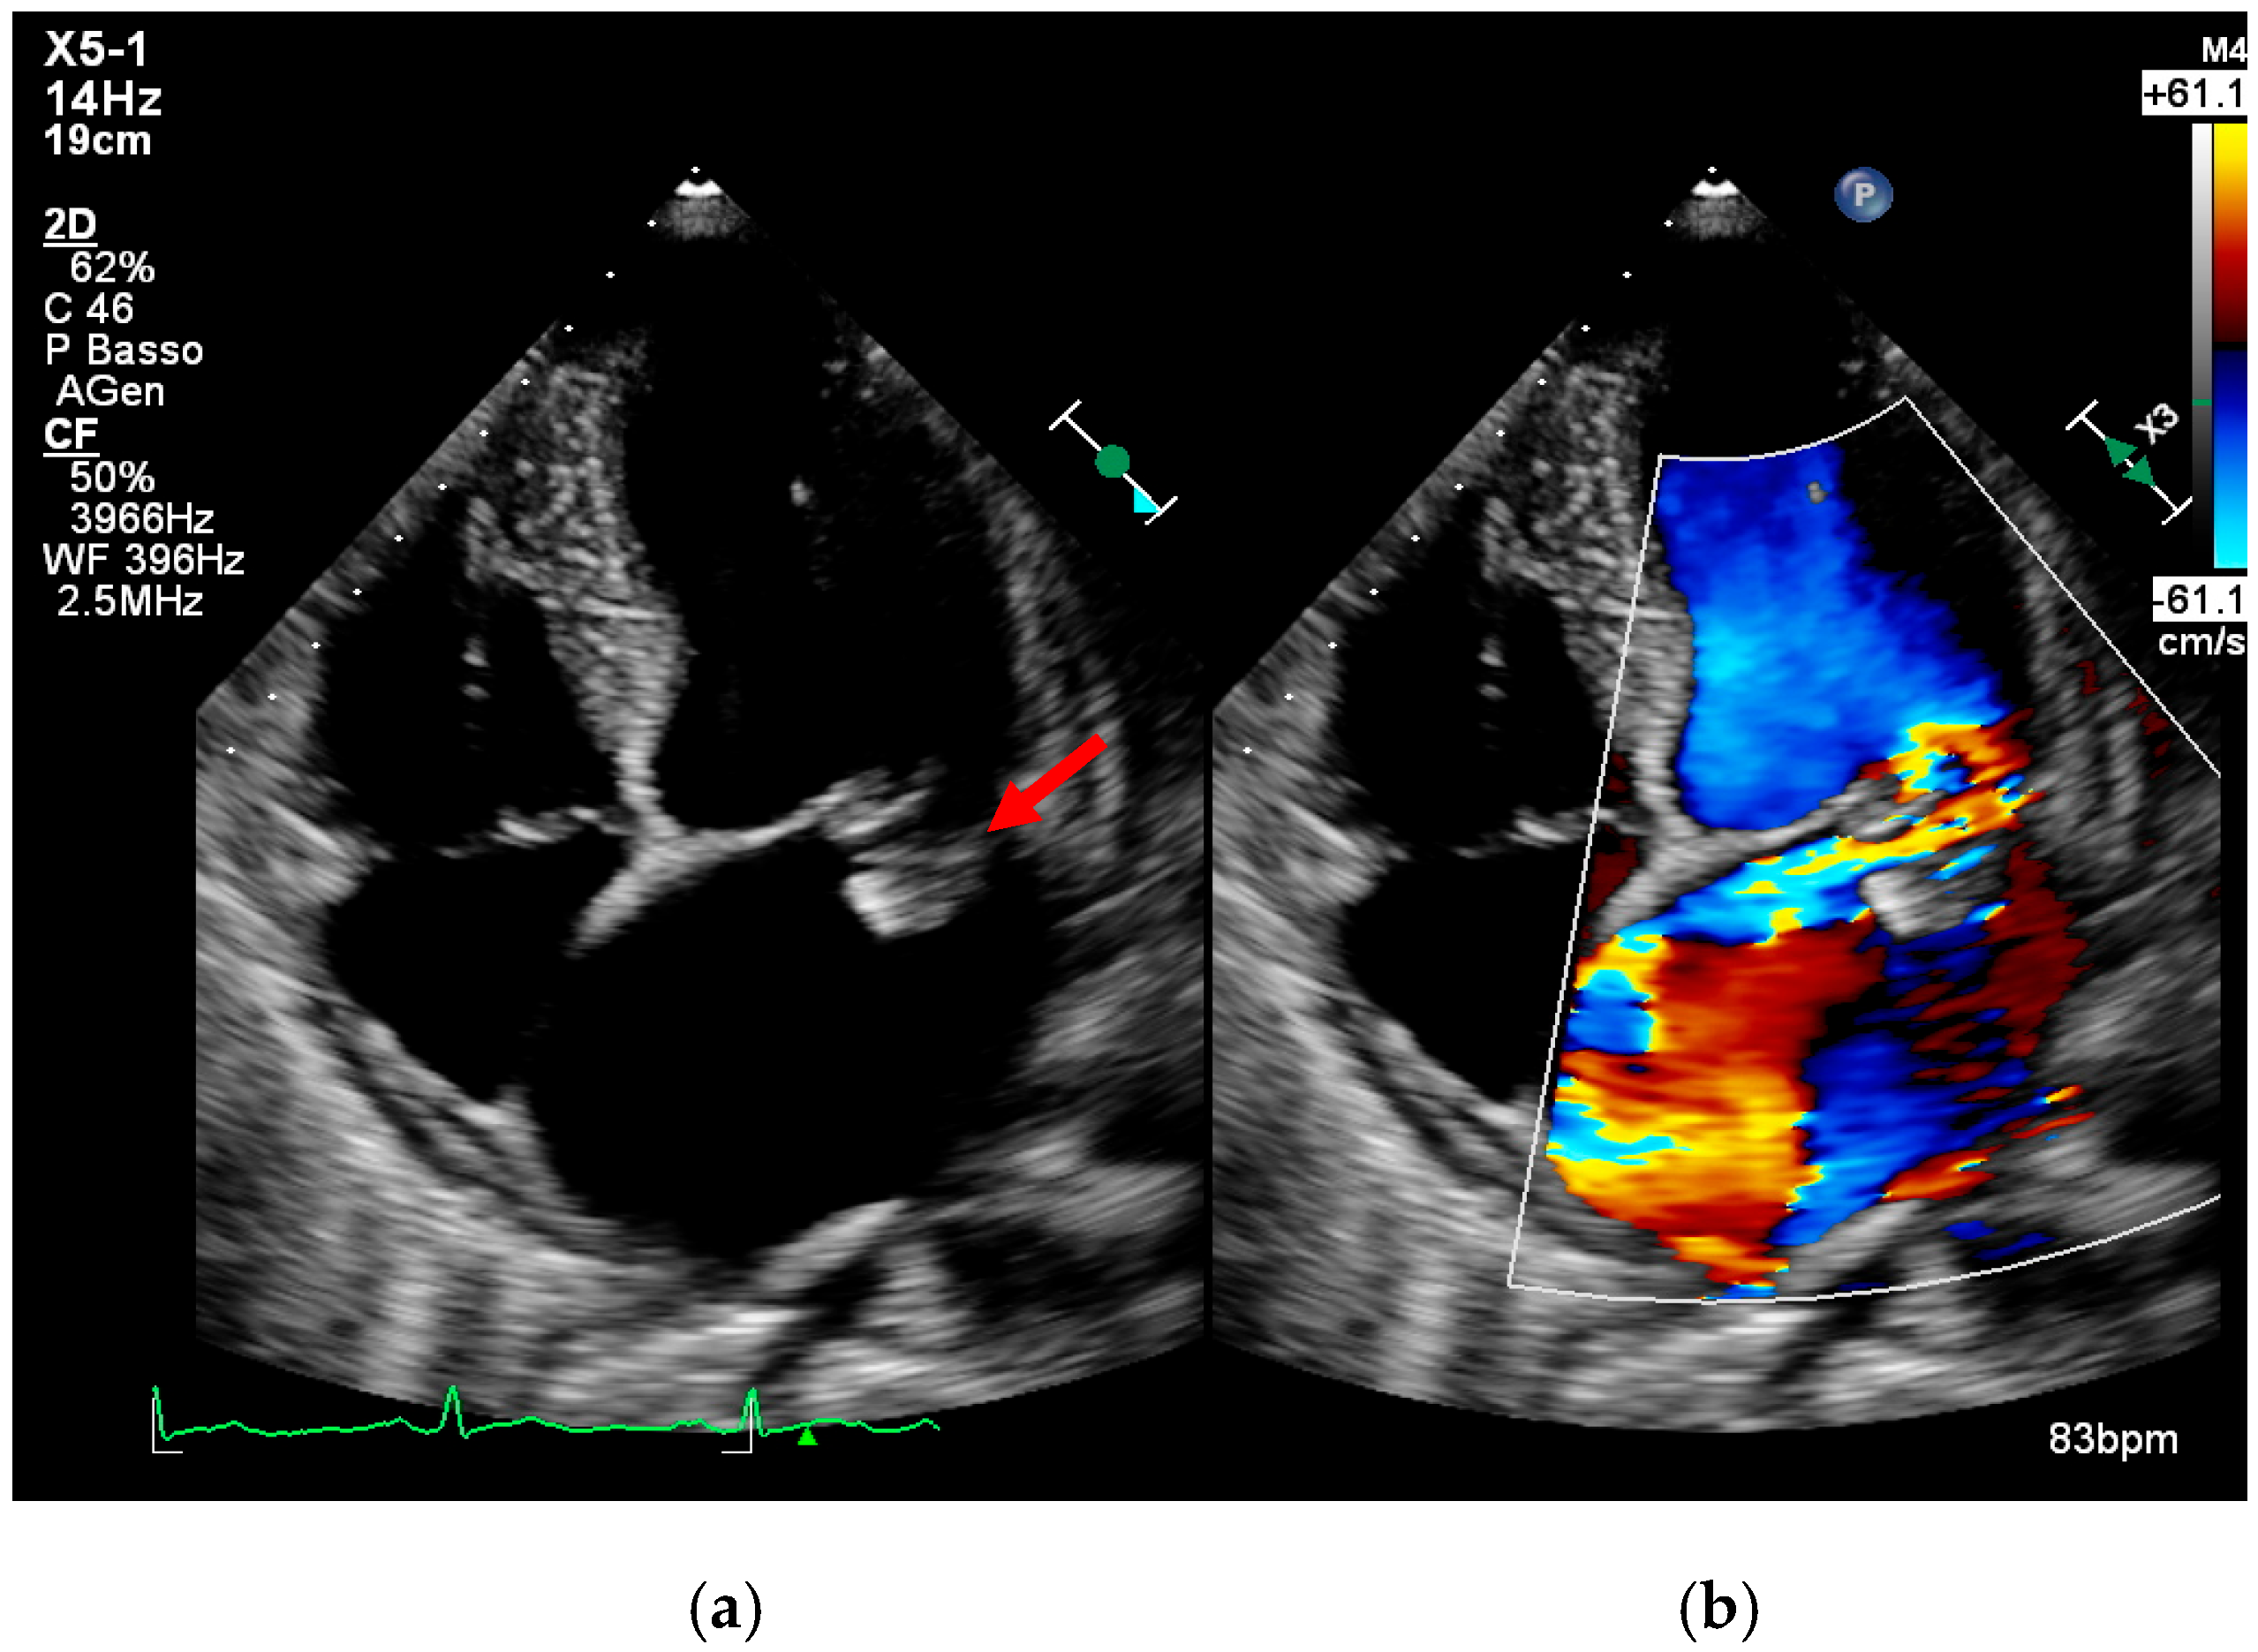

4. Echocardiography

- intracardiac fistula, visualized as an abnormal communication between cardiac chambers or vessels, is often detected by using color Doppler.

- significant new valvular regurgitation compared with previous imaging, i.e., increase in regurgitant jet size, vena contracta width…